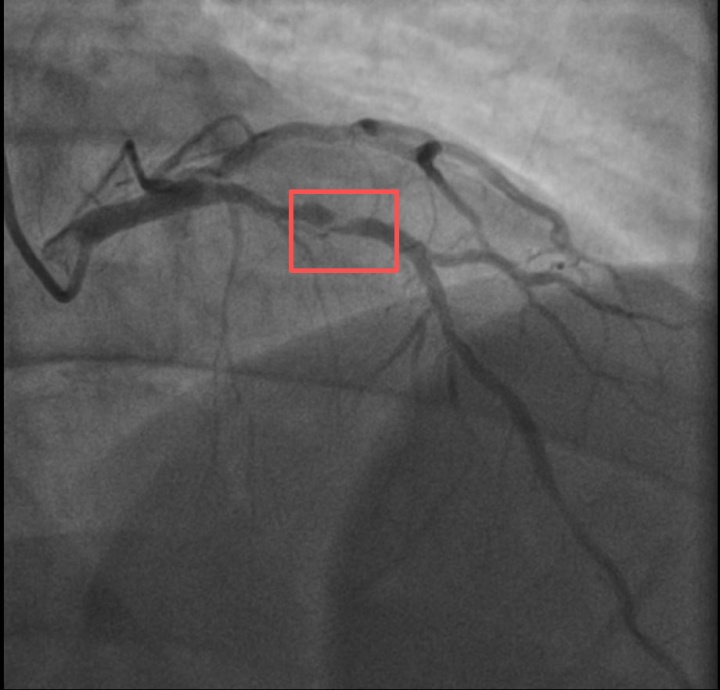

孙先生(化名)是一位羽毛球教练。一年前,他因胸闷就诊时被查出心脏右冠中段、远端钙化斑块,以及心脏三支主要血管之一前降支中段60%狭窄。当时考虑到没有三高的危险因素(可能为早发冠心病家族史),孙先生也坚信自己可以通过运动恢复健康,因此拒绝了介入治疗,只接受药物治疗。

孙先生介入治疗前影像图

孙先生花了一年时间,体重从原来的96公斤瘦到90公斤,但让他没想到的是,意外还是来了。近日,他带孩子去练习羽毛球,没想到亲自上场挥杆仅10分钟左右,孙先生就因心前区剧烈绞痛被送进了急诊。

浙江医院心血管内科的医生分析,剧烈运动导致这位患者心脏的不稳定斑块破裂,进而造成前降支近段次全闭塞。所幸送医及时,孙先生的身体险情被化解。

介入治疗后影像图